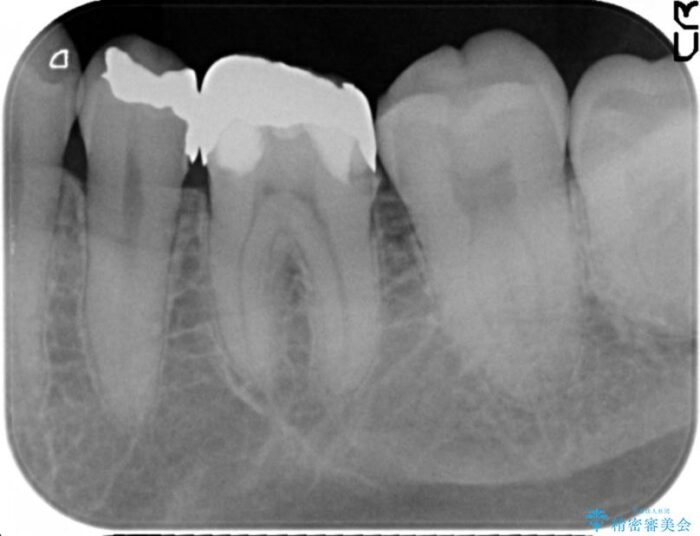

銀歯の適合や形態不良により、食べ物が非常に挟まりやすく、虫歯の再発も銀歯の下に認められる状態でした。

不適合な修復物、虫歯の除去を丁寧におこなったのち、清掃しやすい形態へと回復する精密なセラミック治療を行います。